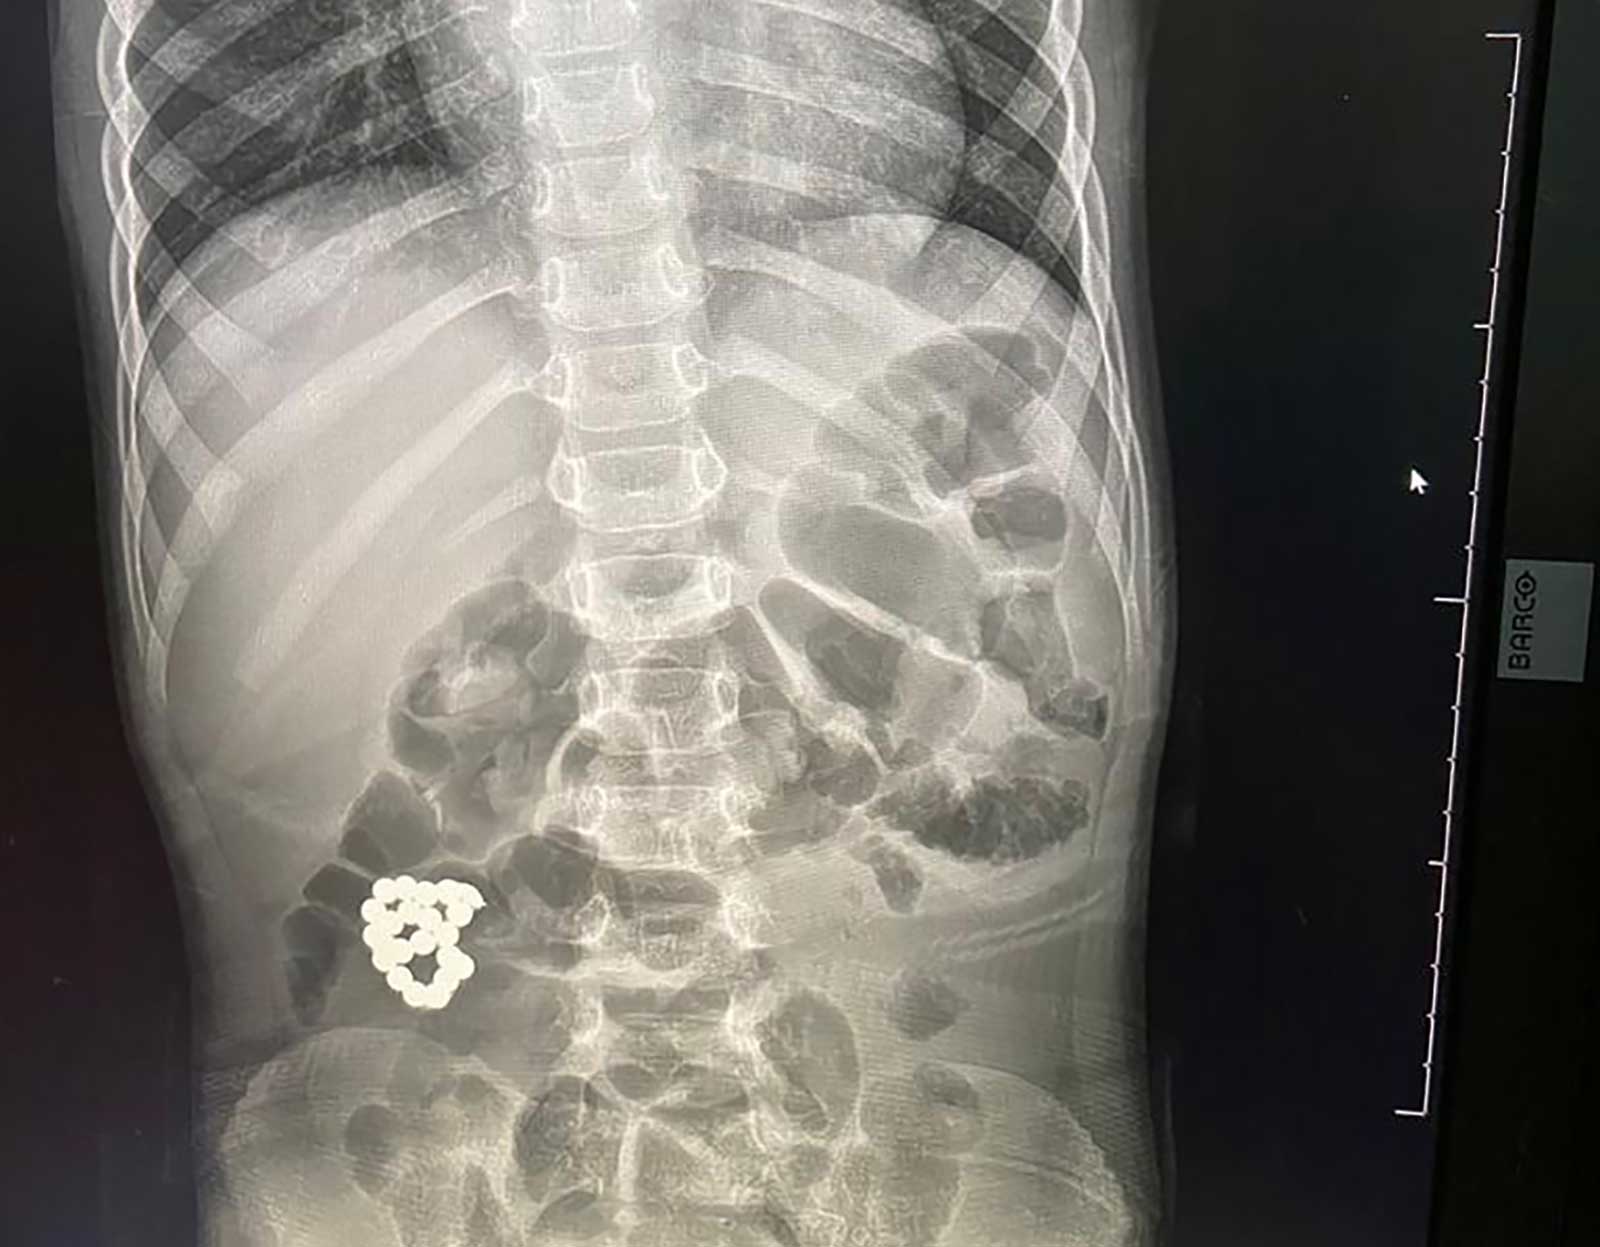

وبعد إجراء الفحوصات اللازمة، أظهرت صور الأشعة وجود جسم غريب في الأمعاء، تبين أنها"إسوارة".

وتم إدخال الطفل فوراً لغرفة العمليات واستخراج الجسم الغريب، وجرى استئصال الأجزاء المتضررة من الأمعاء في عملية استغرقت ساعتين ونصف الساعة، تكللت بالنجاح.